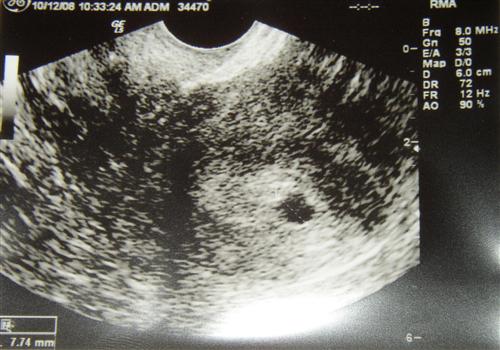

Meet Our Spot...

Our new baby's name is Spot....

Here is our Spot....grow Spot, grow!

The 'spot' is the gestational sac... The dashes across the 'sac' is the ruler....they measured and the sac is 7.74mm.

5 weeks, 3 days today. Bloodwork VERY good....

HCG: 4,851 Progesterone: 20